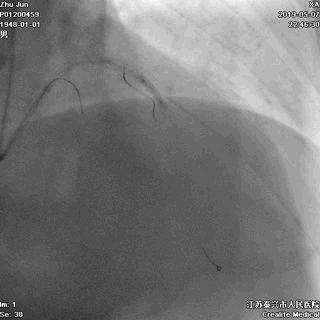

三、球囊扩张病变

---打通生命通道

前降支至左主干行PTCA

四、STENT植入

---巩固胜利成果

前降支植入第一枚STENT

前降支-左主干STENT定位和植入